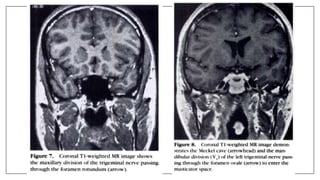

Boundaries of Meckel’s Cave

• The cerebellar tentorium superolaterally

• The lateral wall of the cavernous sinus superomedially

• The clivus medially

• The posterior petrous face inferolaterally